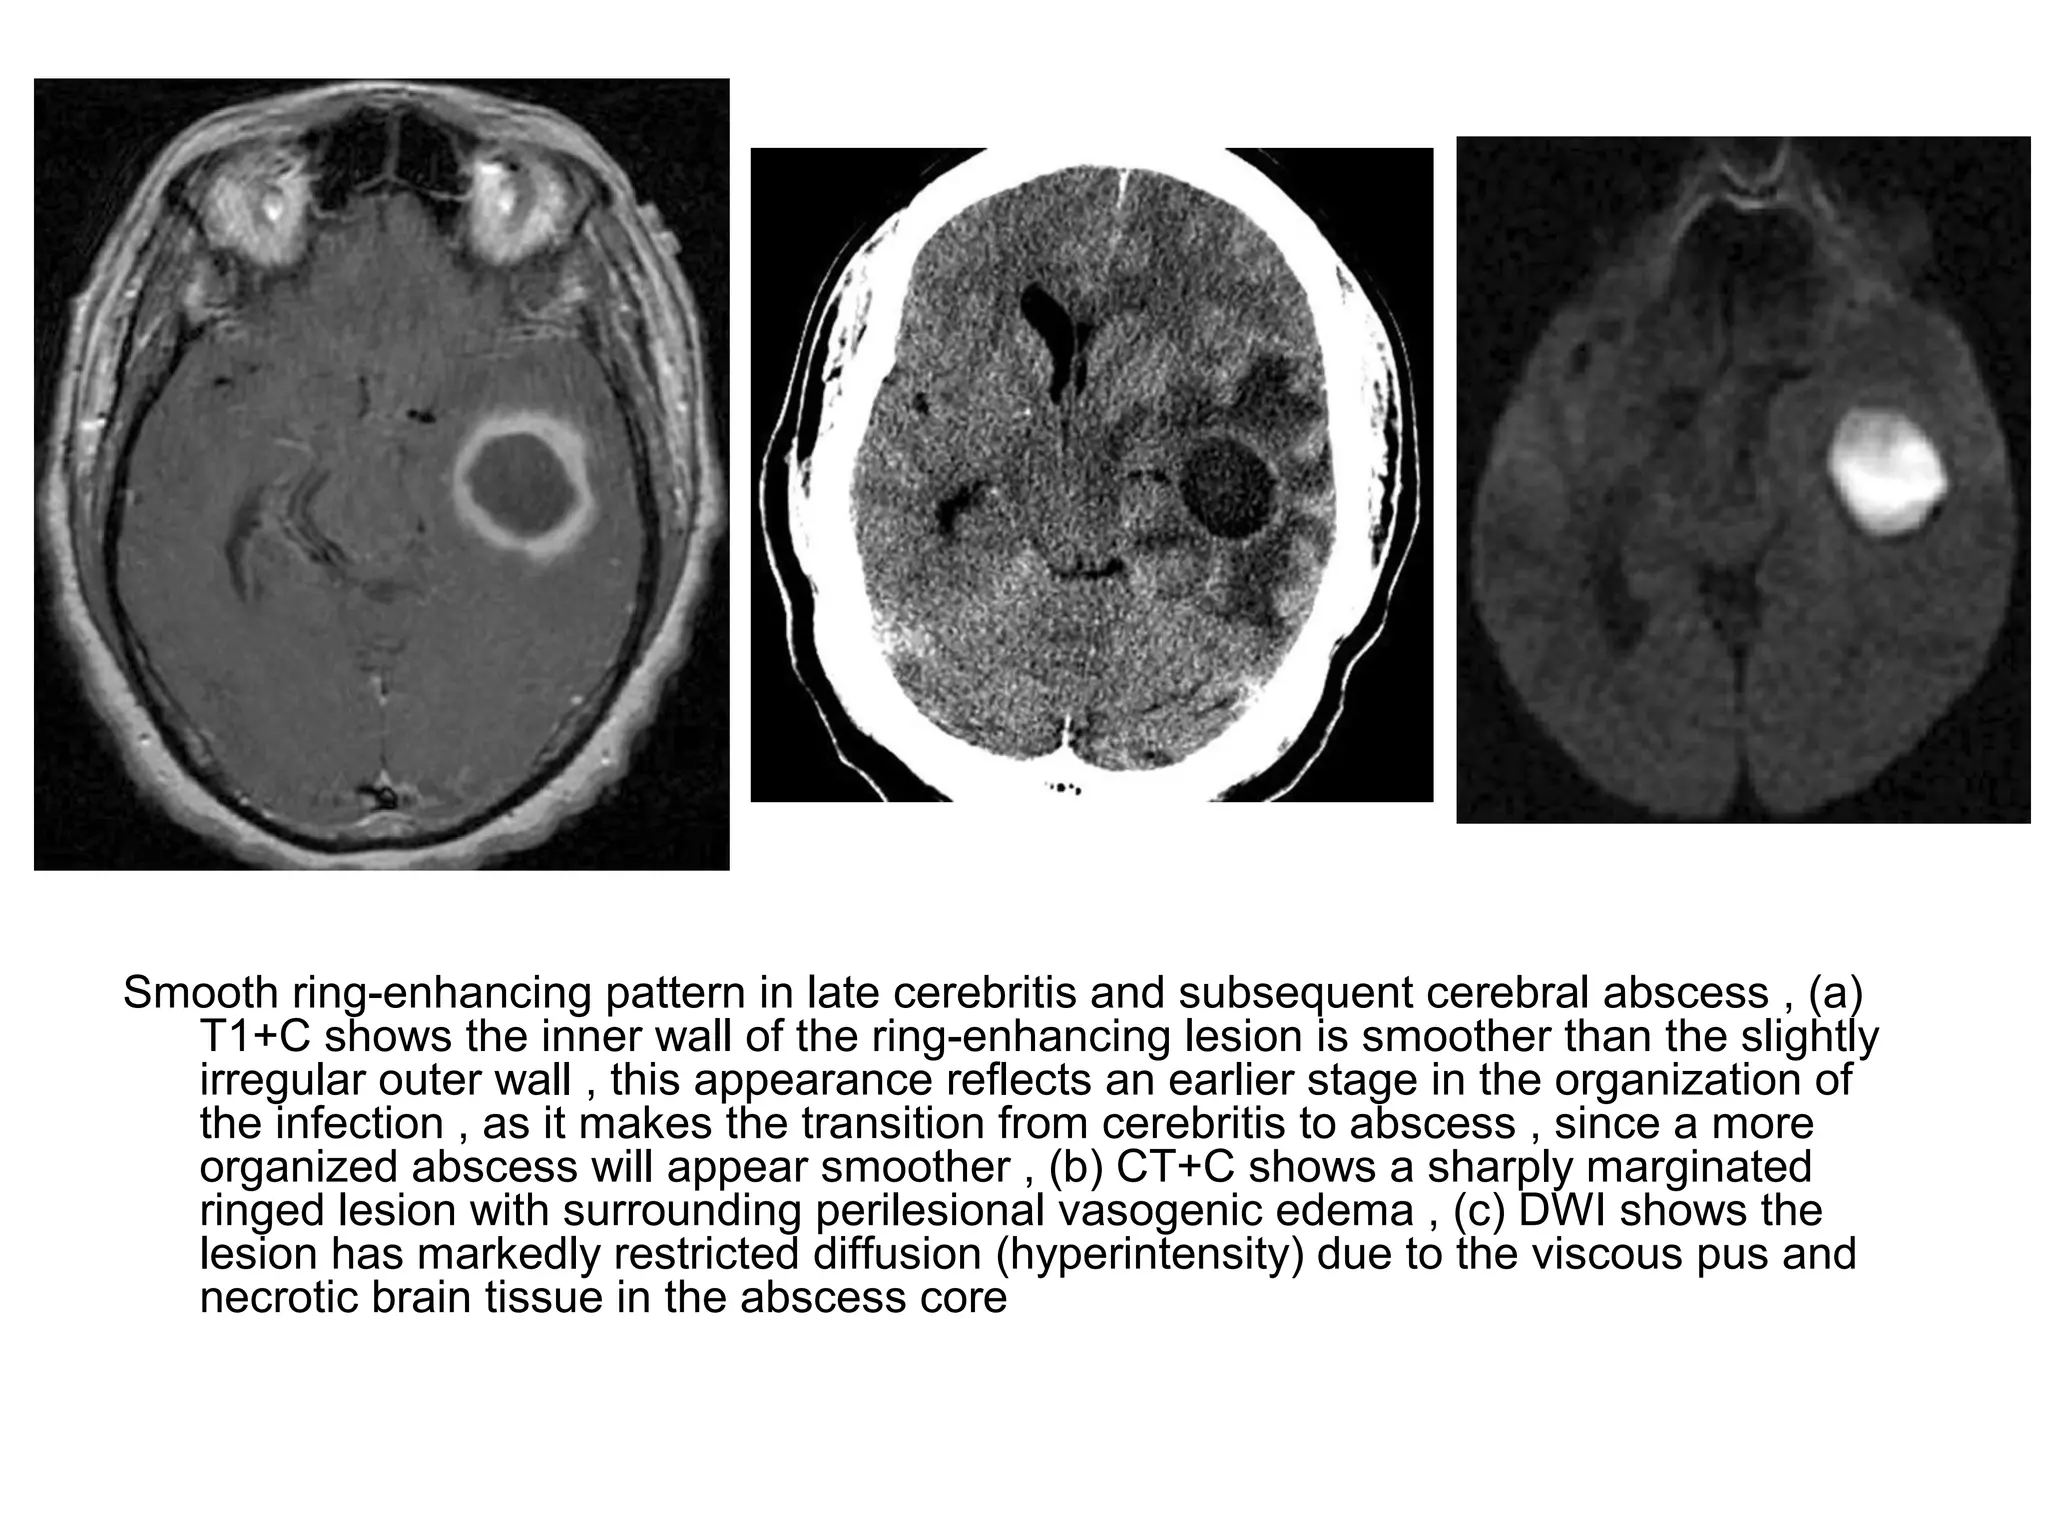

Smooth ring-enhancing pattern in late cerebritis and subsequent cerebral abscess , (a)

T1+C shows the inner wall of the ring-enhancing lesion is smoother than the slightly

irregular outer wall , this appearance reflects an earlier stage in the organization of

the infection , as it makes the transition from cerebritis to abscess , since a more

organized abscess will appear smoother , (b) CT+C shows a sharply marginated

ringed lesion with surrounding perilesional vasogenic edema , (c) DWI shows the

lesion has markedly restricted diffusion (hyperintensity) due to the viscous pus and

necrotic brain tissue in the abscess core